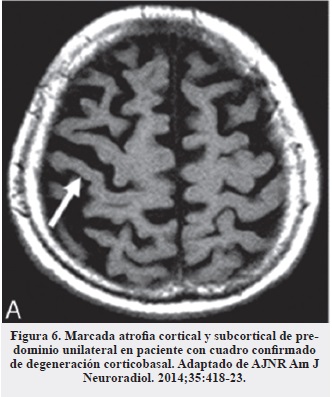

En nuestro caso la realización de la resonancia de cerebro constituyó una herramienta muy útil que, además de argumentar la sospecha clínica inicial, sirvió para descartar otras lesiones estructurales asociadas a caídas frecuentes (hematomas, hidrocefalia a presión normal, etc. ). Los hallazgos característicos de esta enfermedad son, principalmente, la atrofia del tegmento del mesencéfalo (Figura 2) en proyección sagital (signo del colibrí o del pingüino) (Figura 3) (16, 17), la alteración del diámetro anteroposterior y la atrofia generalizada del mesencéfalo (Figura 4) (18).

En el diagnóstico diferencial con degeneración corticobasal es importante buscar la atrofia cortical marcada unilateral característica de esta entidad (Figura 6) (17, 19) y de las afasias primarias progresivas y ausentes en la PSP, en las que la atrofia es más generalizada (17).